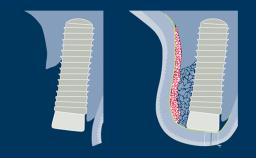

Surgical Planning and Procedures

Principles of Guided Bone Regeneration (GBR)

Learning Module

Surgical Planning and Procedures

Simultaneous Contour Augmentation Using GBR

Learning Module